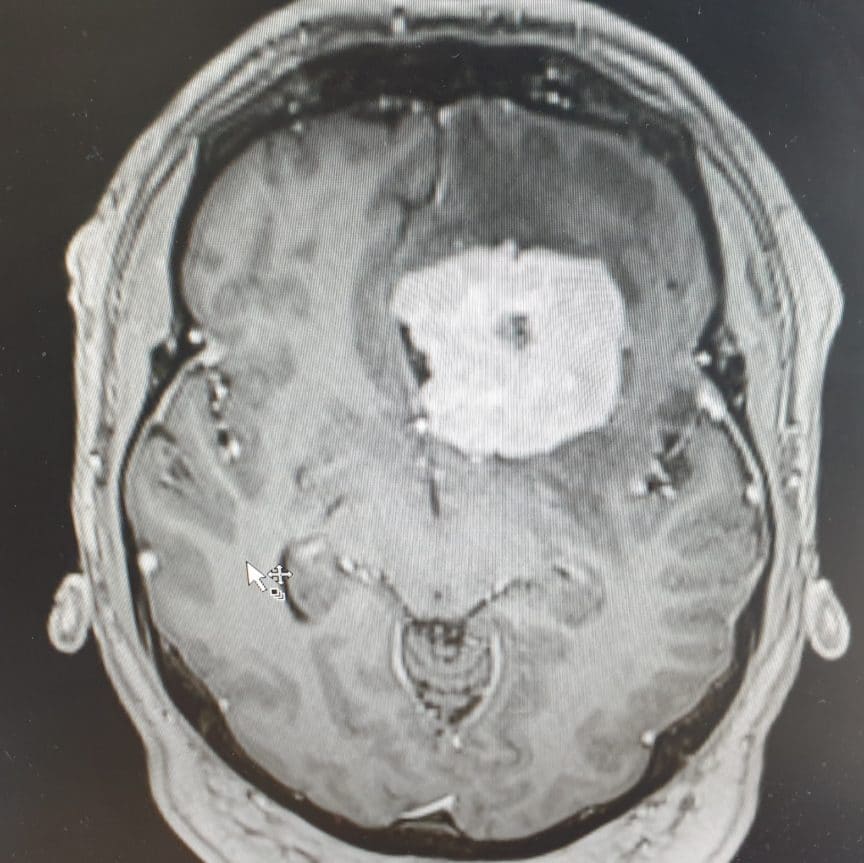

Tennis Ball Size Brain Tumour . in july, 2013, i had the shock of my life when after having headaches for a few months, i was diagnosed with a golf ball size tumor. the tumor was connected to my main brain stem and pushed its way up. yvette was told that she had a brain tumour the size of a tennis ball and that she needed to have surgery to remove it. the signs and symptoms of a brain tumor depend on the brain tumor's size and location. this got me a ride in a magnetic resonance imaging machine, which revealed a brain mass the size of a tennis. ruth stevens was shocked to learn she had a tumor in her brain the size of a. After spending a few nights in icu i was.

Tennis Ball Size Brain Tumour the signs and symptoms of a brain tumor depend on the brain tumor's size and location. this got me a ride in a magnetic resonance imaging machine, which revealed a brain mass the size of a tennis. After spending a few nights in icu i was. in july, 2013, i had the shock of my life when after having headaches for a few months, i was diagnosed with a golf ball size tumor. yvette was told that she had a brain tumour the size of a tennis ball and that she needed to have surgery to remove it. the tumor was connected to my main brain stem and pushed its way up. the signs and symptoms of a brain tumor depend on the brain tumor's size and location. ruth stevens was shocked to learn she had a tumor in her brain the size of a.

3d brain mri classification Tennis Ball Size Brain Tumour in july, 2013, i had the shock of my life when after having headaches for a few months, i was diagnosed with a golf ball size tumor. the tumor was connected to my main brain stem and pushed its way up. After spending a few nights in icu i was. this got me a ride in a. Tennis Ball Size Brain Tumour.

A tennis ballsized brain tumor UF Health Neurosurgery YouTube Tennis Ball Size Brain Tumour the signs and symptoms of a brain tumor depend on the brain tumor's size and location. yvette was told that she had a brain tumour the size of a tennis ball and that she needed to have surgery to remove it. this got me a ride in a magnetic resonance imaging machine, which revealed a brain mass. Tennis Ball Size Brain Tumour.